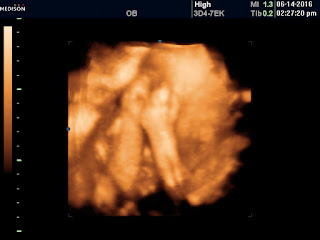

How far along: 29 Weeks

Gender:Boy (:

Best moment this week: Seeing out little man in the 3D Ultrasound, it's insane how much he looks like Cameron already.